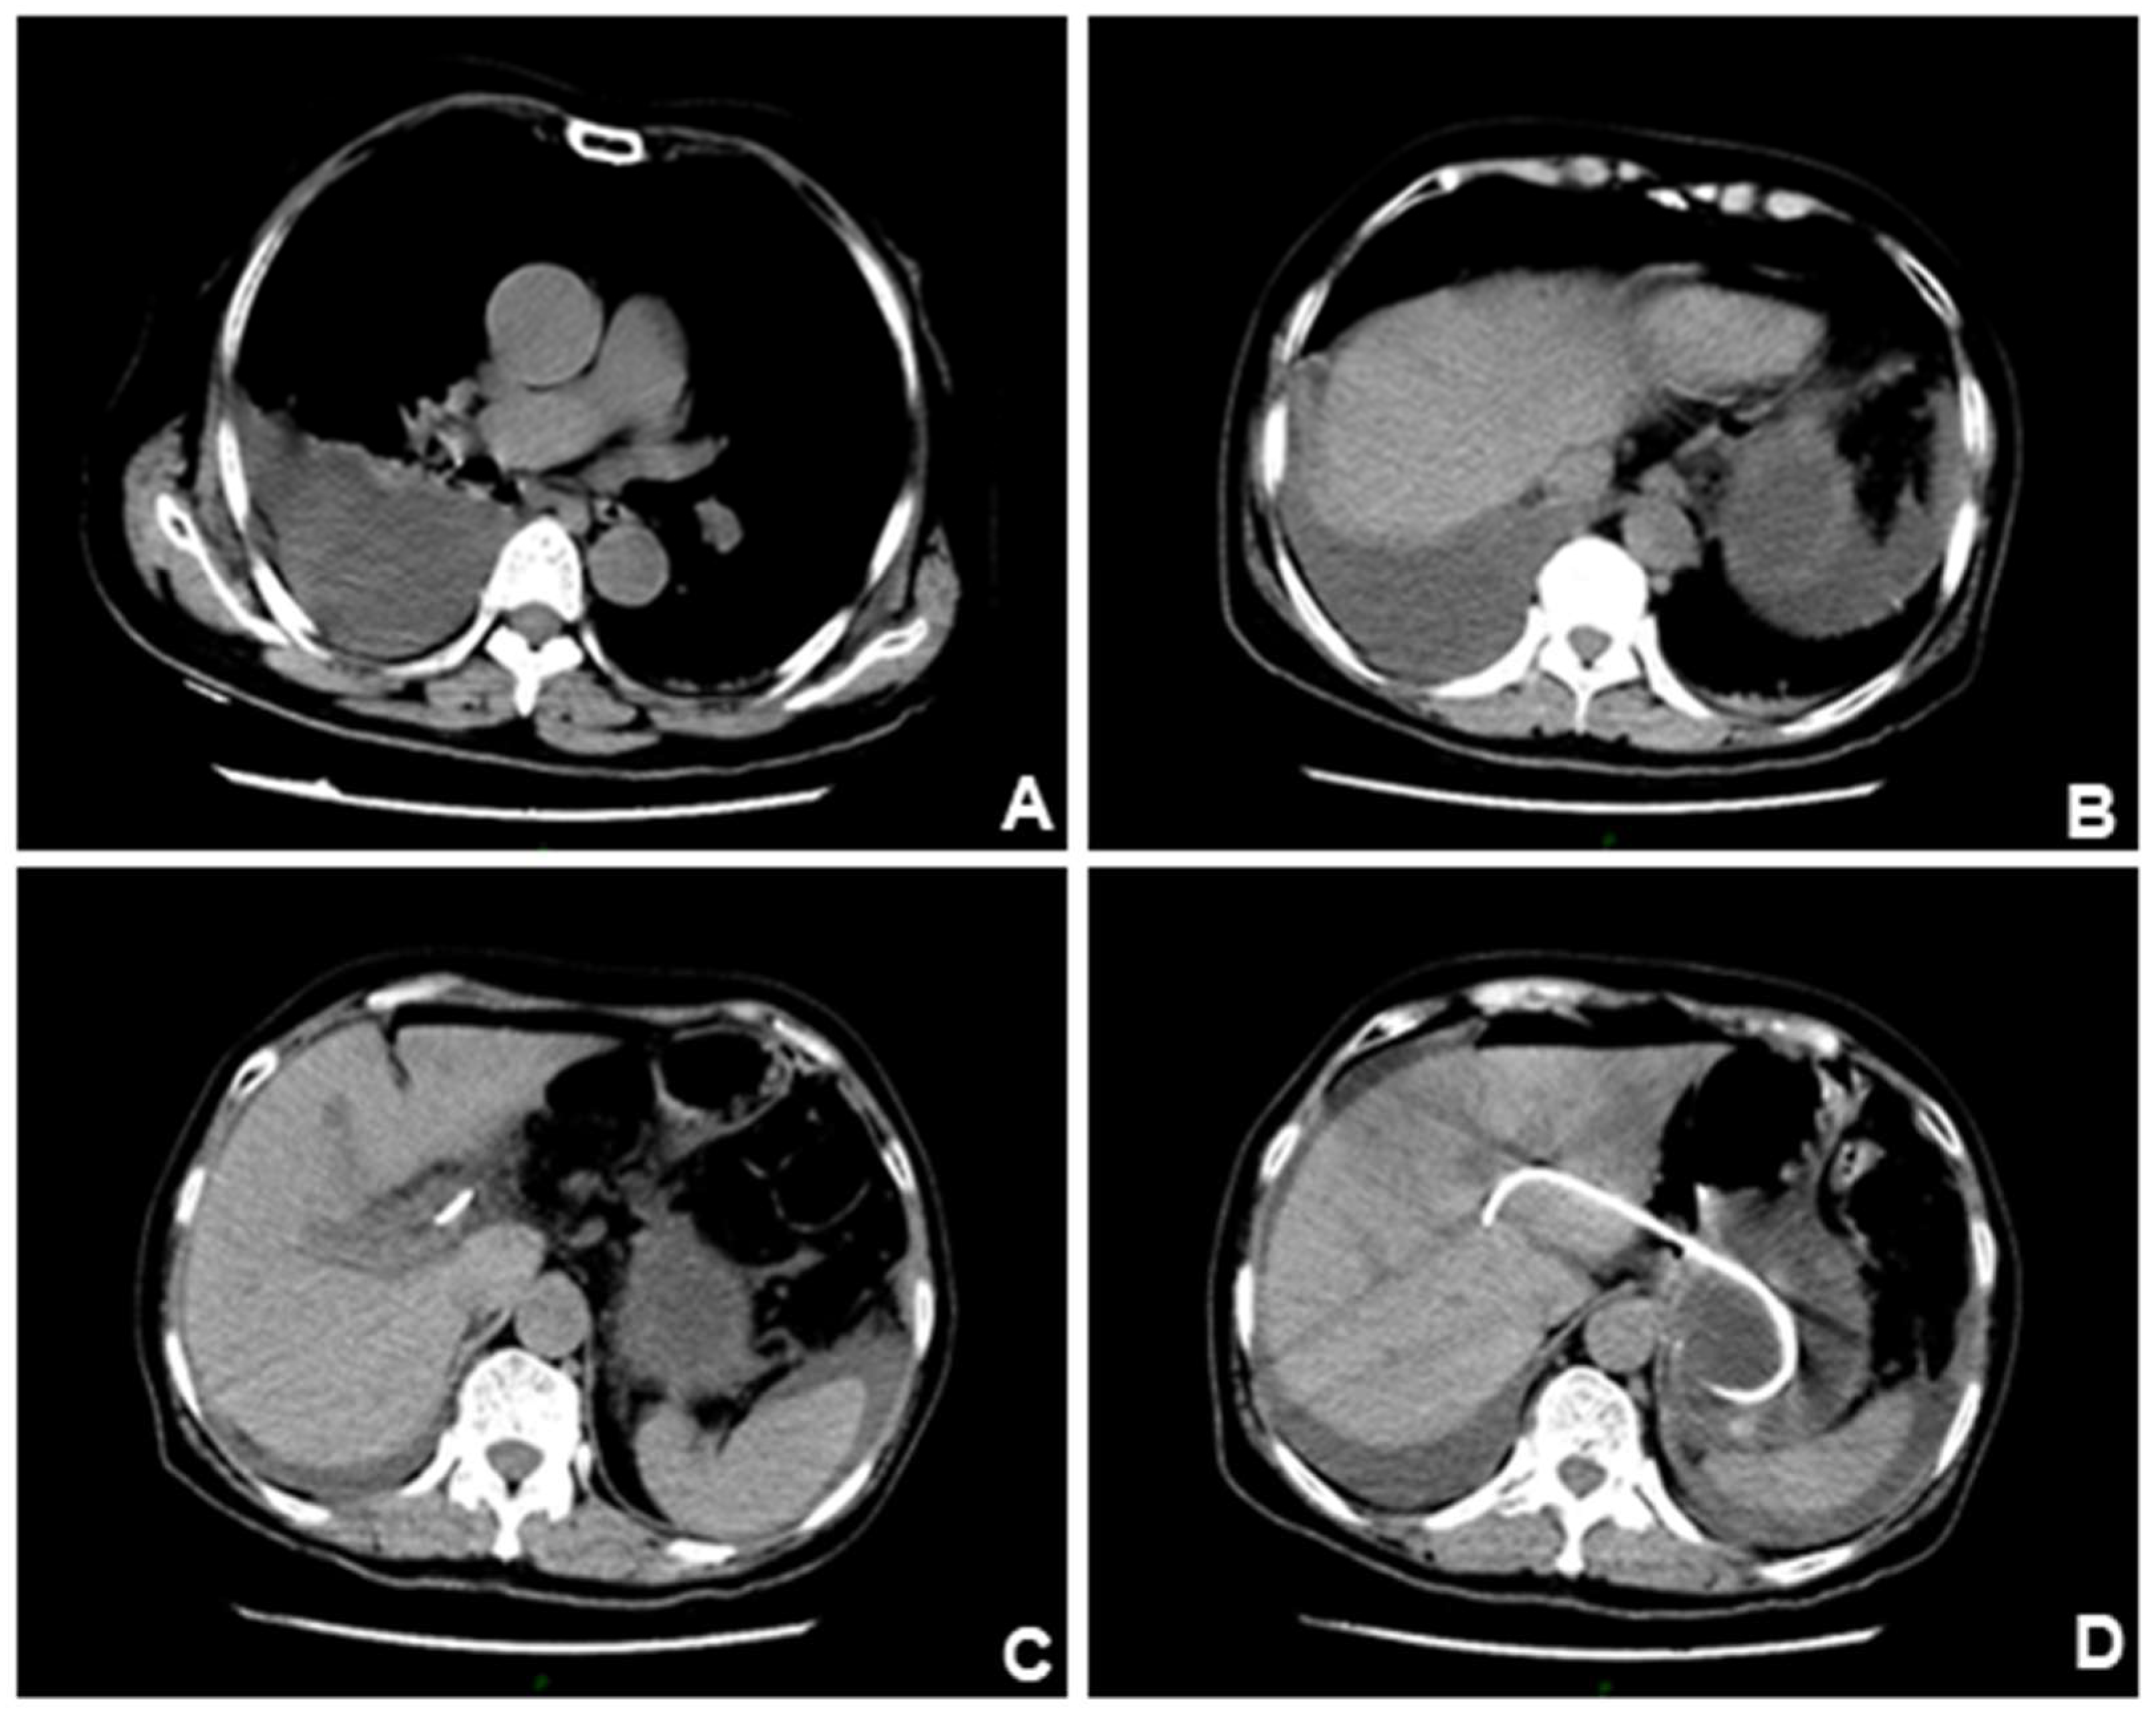

Figure 4.

However, CT scan performed one week later showed a significant increase of ascites, and the previous pleural effusion basically disappeared. Position of the stent under X-ray and CT scan. (A). The position of the stent was far from the lung, so it was considered that the diaphragm had been accidentally injured intraoperatively. (B-C). The pleural effusion gradually disappeared after closed drainage.